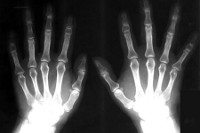

Болезнь Тиманна. Наследственный асептический остеонекроз фаланг пальцев кистей. В гораздо более редких случаях встречается аналогичное поражение стоп. Болезнь Тиманна проявляется в основном припухлостью в области межфаланговых суставов нескольких пальцев на обеих руках. Припухлость имеет веретенообразную форму и не сопровождается воспалительными симптомами. Диагностика болезни Тиманна состоит в рентгенографии костей кисти и проведении лабораторных исследований (клинический анализ крови, определение в крови РФ и СРБ) для исключения инфекционного и ревматического поражения суставов. Проводится симптоматическое лечение заболевания консервативными методами: фиксирующая повязка, массаж, физиотерапия.

В большинстве случаев болезнь Тиманна протекает с поражением эпифизов средних фаланг, входящих в проксимальные межфаланговые суставы среднего, безымянного и указательного пальцев. Реже патологические изменения наблюдаются в дистальных межфаланговых суставах. Обычно асептический некроз развивается одновременно в 2-3 пальцах одной кисти. При этом характерно несимметричное поражение пальцев обеих рук. В отдельных случаях некротические изменения наблюдается в тарзометатарзальном суставе и межфаланговом суставе 1-го пальца стопы.

При осмотре у пациентов, имеющих болезнь Тиманна, наблюдается веретенообразная припухлость проксимальных или дистальных межфаланговых суставов пальцев рук. Как правило, в начале заболевания патологические изменения отмечаются только в области среднего пальца. Постепенно некрозу подвергаются эпифизы средних фаланг и других пальцев, однако большой палец руки всегда остается интактным.

Диагностировать болезнь Тиманна может травматолог, ортопед или ревматолог. Однако диагностика заболевания в раннем периоде его развития весьма затруднительна. По этой причине больные часто проходят лечение с диагнозами «артрит», «тендовагинит», «растяжение». Лишь со временем развитие некротического процесса приводит к формированию характерной деформации межфаланговых суставов, выявляемой при рентгенологическом обследовании. Рентгенография костей кисти определяет уплощение, резорбцию и дефрагментацию эпифизов пораженных фаланг. При большой длительности болезни Тиманна могут наблюдаться рентгенологические признаки деформирующего остеоартроза: сужение суставной щели межфалангового сустава, субхондральный остеосклероз, разрастание остеофитов.